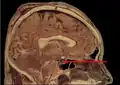

Сагиттальный срез черепа, гипофиз окрашен розовым: слева — аденогипофиз, справа — нейрогипофиз

Гипофиз состоит из двух крупных различных по происхождению и структуре долей: передней — аденогипофиза (составляет 70—80 % массы органа) и задней — нейрогипофиза. Вместе с нейросекреторными ядрами гипоталамуса гипофиз образует гипоталамо-гипофизарную систему, контролирующую деятельность периферических эндокринных желёз.